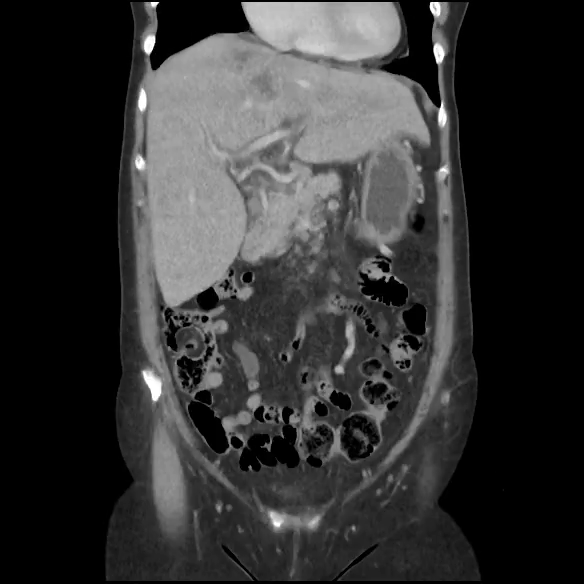

La paciente ingresa a cargo de cirugía y durante la hospitalización se le realiza TAC toracoabdominal que corrobora los hallazgos vistos mediante la ecografía, y añade linfadenopatías, una imagen de aspecto también metastásico suprarrenal izquierdo y engrosamiento focal de paredes gástricas de aspecto neoproliferativo.